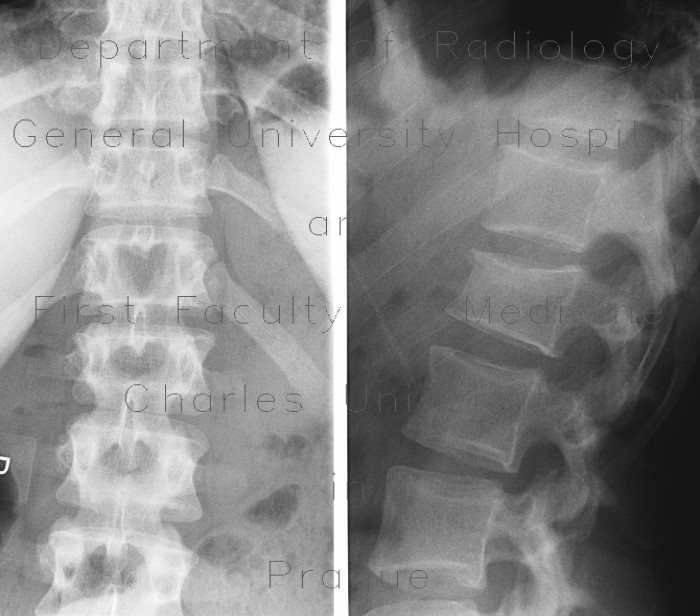

Fractures Of The Thoracic And Lumbar Spine - OrthoInfo - AAOS

Fractures of the Thoracic and Lumbar Spine - OrthoInfo - AAOS 15/09/12 9:10 AM A CT scan taken from the side of a burst fracture in the lumbar spine. Treatment The treatment plan for a fracture of the thoracic or lumbar spine will depend on: ... Retrieve Content